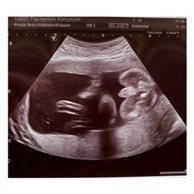

ท้องเกือบ7เดือนแล้ว ส่วนตัวเรารู้สึกว่าลูกเป็นผชมาตลอด แต่ซาว2ครั้งแล้ว(ซาวล่าสุด5เดือนกว่าคะ)คุนหมอก็บอกผญ แม่บ้านไหนเคยเป็นแบบเราบ้างแล้วผลสรุปออกมาตรงกับคุณหมอมั่ยค๊ะ

แบบนี้ ผู้หญิง หรือ ผู้ชายคะแม่ๆช่วยดูหน่อยค่ะ

ดูจากรูปซาวน์น่าจะเป็นลูกสาว

แบบนี้ผญหรือผชคะ ดูไม่เป็น😅